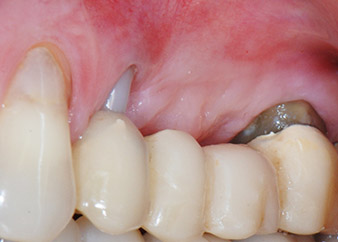

Résultat intermédiaire à deux mois

Les figures 17 et 18 présentent le résultat clinique deux mois après l'intervention chirurgicale. La dent 24 présentait une mobilité réduite, de classe I (Miller) et les tissus mous ne présentaient aucune inflammation. Pour prévenir toute nouvelle infection et pour éviter d'endommager l'attache épithéliale, aucun test n'a été pratiqué à ce stade. Une visite de contrôle a été programmée pour la prochaine incision et la mise en place des parties secondaires de cicatrisation, six mois après l'insertion des implants.